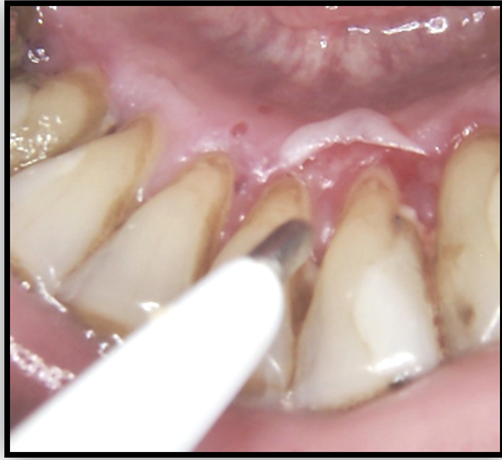

Oral mucosal involvement is common, although the reported prevalence in several series of cases has ranged from 8% to 39%. The oral lesions, the same as the skin lesions, begin as bullae, but they have tend to rupture sooner, probably as a result of the constant low-grade trauma in oral cavity to which the oral mucosa is subjected. Large, shallow ulcerations with smooth, distinct margins are present after the bullae rupture [4, 7, 8].

During the scheduled visit to dental office a 54-year-old male was diagnosed with bullae in vestibular aspect of right maxilla. He was reported to the outpatient Department of Oral and Maxillofacial surgery, FDM, MU - Sofia, with a chief complaint of bullae. He has no history of difficulty in swallowing food or any eyesight problems. On general physical examination there were not any complaints and findings. On intraoral examination, a solitary intact bullae measuring about 5 mm in diameter was present on the upper labial mucosa.(Fig.1.) No other bullae and vesicles were founded. Based on patient's history and clinical presentation, a provisional diagnosis of mucous membrane pemphigoid was considered. After the rupture of bullae it left large, superficial, ulcerated, and denuded areas of mucosa.

After some days others lesions were presented in oral mucosa-Fig.2-a,b, fig.3